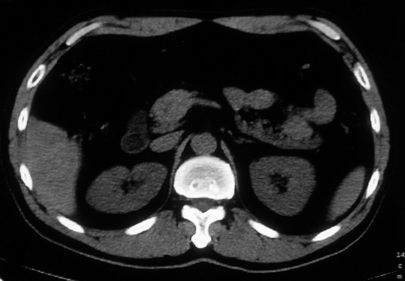

男,体查发现右肝低密度,右肾高密度结节影。高密度ct值92hu,囊肿?

肝右叶囊肿或血管瘤?右肾高密度囊肿。建议增强。

肝右叶圆形低密度灶,考虑囊肿或血管瘤,建议ct增强检查;右肾包膜下高密度圆形灶,考虑:囊肿并出血